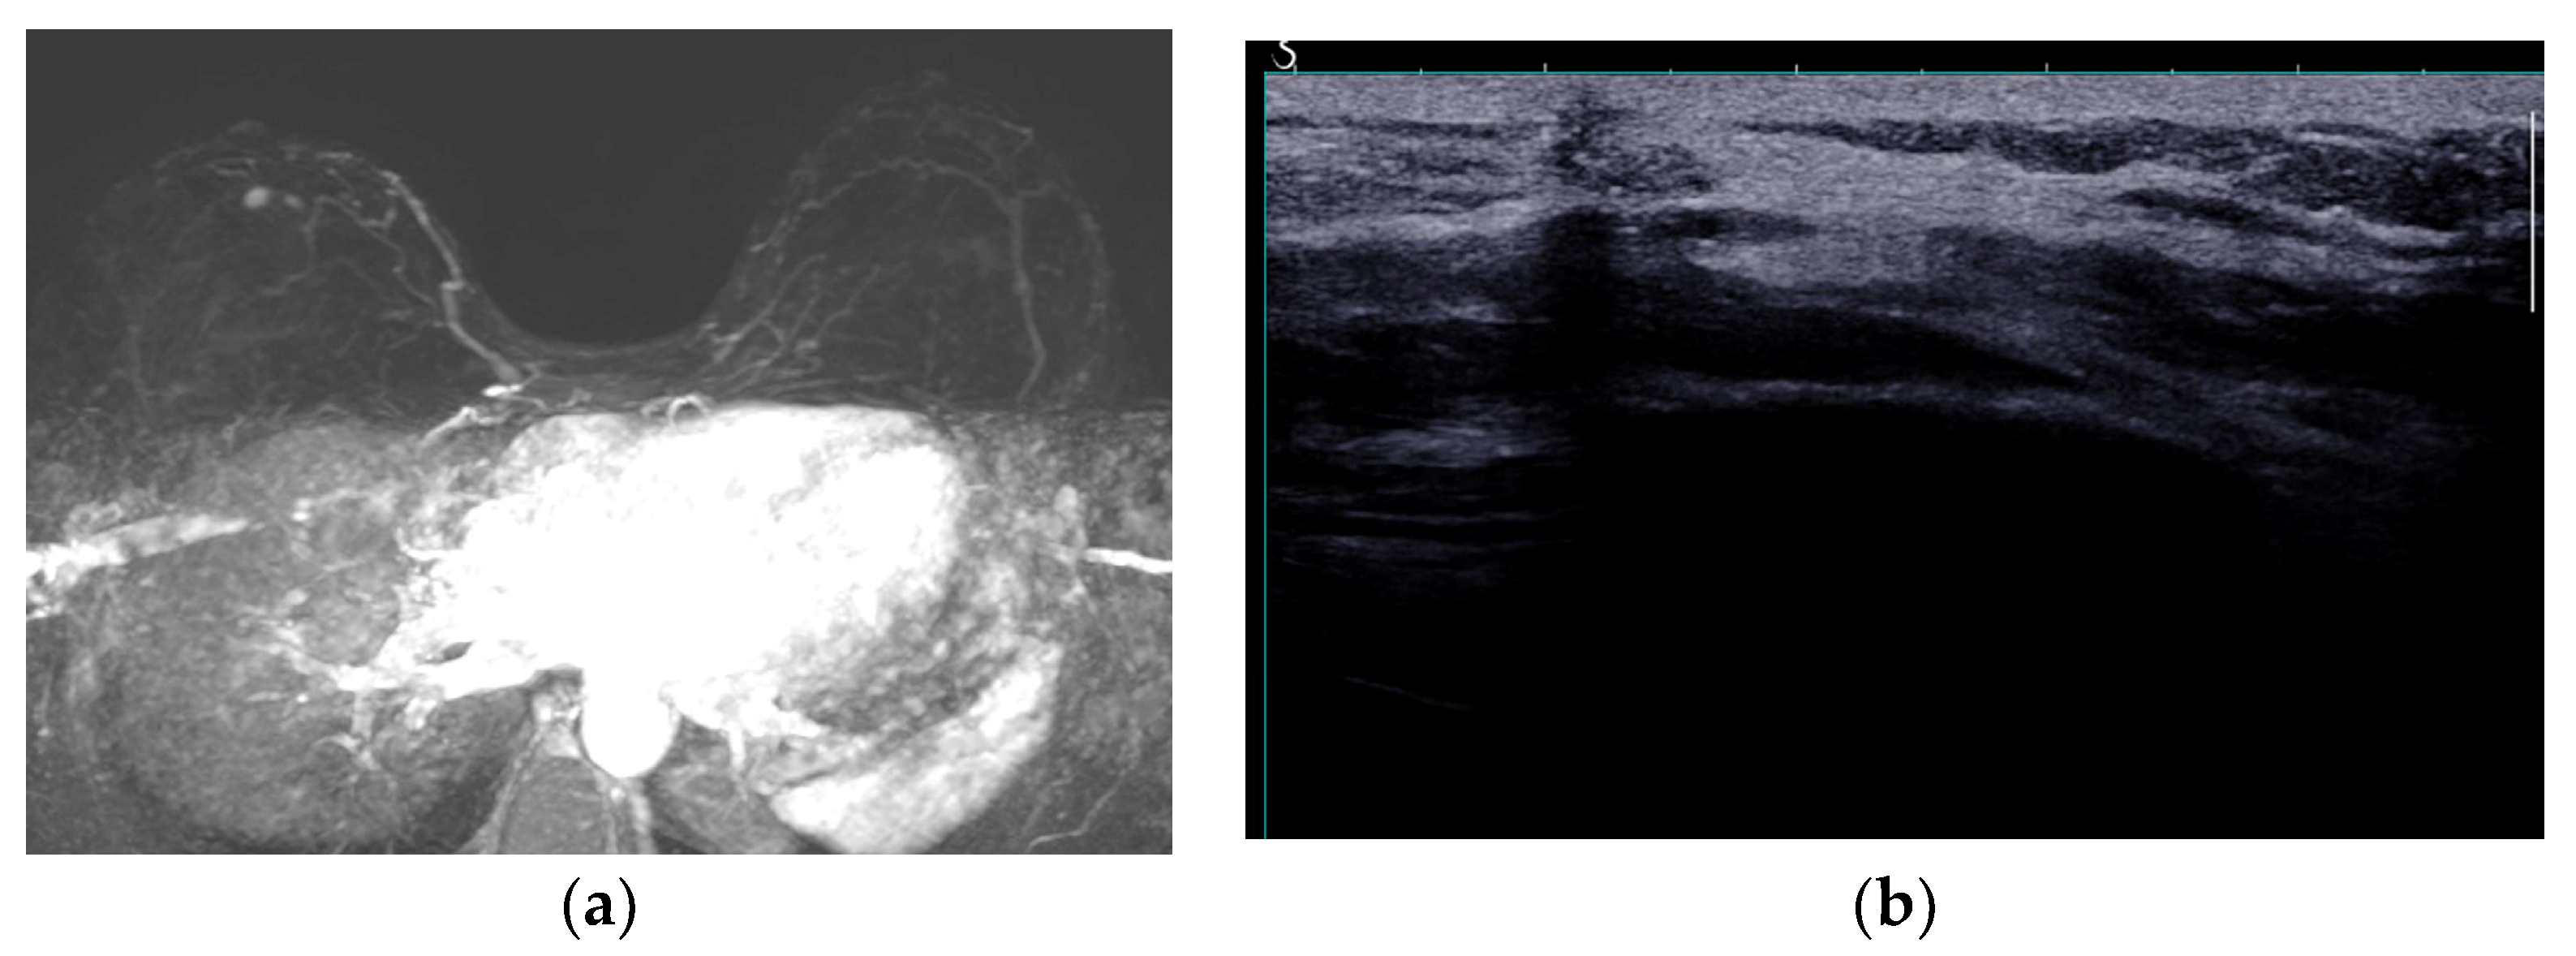

3. Preoperative Imaging

- Vasile, J.V.; Levine, J.L. Magnetic resonance angiography in perforator flap breast reconstruction. Gland. Surg. 2016, 5, 197–211. [Google Scholar] [PubMed]

- Rozen, W.M.; Phillips, T.J.; Ashton, M.W.; Stella, D.L.; Gibson, R.N.; Taylor, G.I. Preoperative imaging for DIEA perforator flaps: A comparative study of computed tomographic angiography and Doppler ultrasound. Plast. Reconstr. Surg. 2008, 121, 9–16. [Google Scholar] [CrossRef]

- Salgarello, M.; Visconti, G. Designing Lateral Thoracic Wall Perforator Flaps for Breast Reconstruction Using Ultrasound. J. Reconstr. Microsurg. 2022, 38, 228–232. [Google Scholar] [CrossRef] [PubMed]